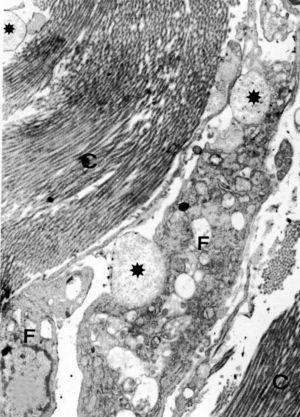

El estudio ultraestructural puso de relieve la presencia en la dermis de abundantes fibroblastos, dispuestos entre gruesos paquetes de fibras de colágeno y amplias formaciones redondeadas de material mucoide (fig. 1). Los fibroblastos mostraban las características de células sumamente activas. Presentaban un núcleo con cromatina laxa y nucléolo evidente, con una membrana doble que mostraba varios poros nucleares (figs. 2 y 3). En el citoplasma destacaba un retículo endoplásmico rugoso prominente, muchas de cuyas cisternas aparecían dilatadas, por lo que le conferían un aspecto vesicular. Así mismo, la dotación mitocondrial era importante, junto a las vesículas con un contenido de baja electrodensidad. En algunos de los fibroblastos se apreciaba cómo liberaban las vesículas de aspecto mucinoso al espacio intercelular (fig. 2). Completaba la elevada actividad de estas células la presencia, en algunas de ellas, de fibras de colágena recién polimerizadas, liberándose mediante la emisión de prolongaciones citoplasmáticas, a modo de pseudópodos (fig. 3) y que una vez en el espacio intercelular, se acoplaban formando gruesos paquetes de colágeno.

Fig. 1.--Sección longitudinal de fibroblasto (F), entre gruesos paquetes de fibras de colágeno (C). *: vesículas de sustancia mucoide. (Aumentos, x7.250.)